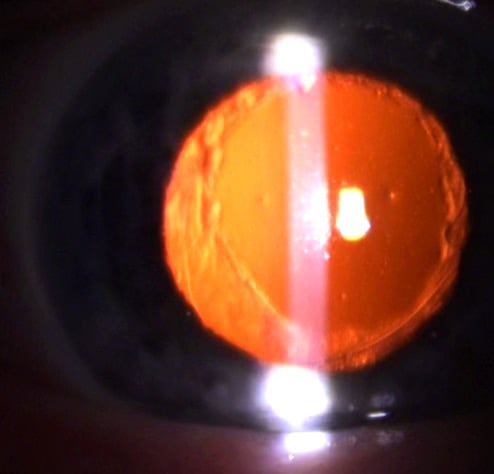

YAG Laser-Behandlung des Nachstars

Mit dem YAG-Laser kann ambulant in der Praxis nach Aufsetzen eines speziellen Kontaktglases in örtlicher Betäubung (Tropfanästhesie) der Nachstar durch zirkuläre, zentrische Eröffnung der hinteren Linsenkapsel dauerhaft entfernt werden, so dass die optische Achse wieder frei wird und das Sehvermögen in der Regel deutlich ansteigt. Der Eingriff kann in Tropfanästhesie ambulant in der Praxis erfolgen, eine Kontrolle am anderen Tag schließt die Behandlung ab. Benefit, Wiederherstellung bzw. Verbesserung des Sehvermögens bei Nachstar Laserbehandlung.